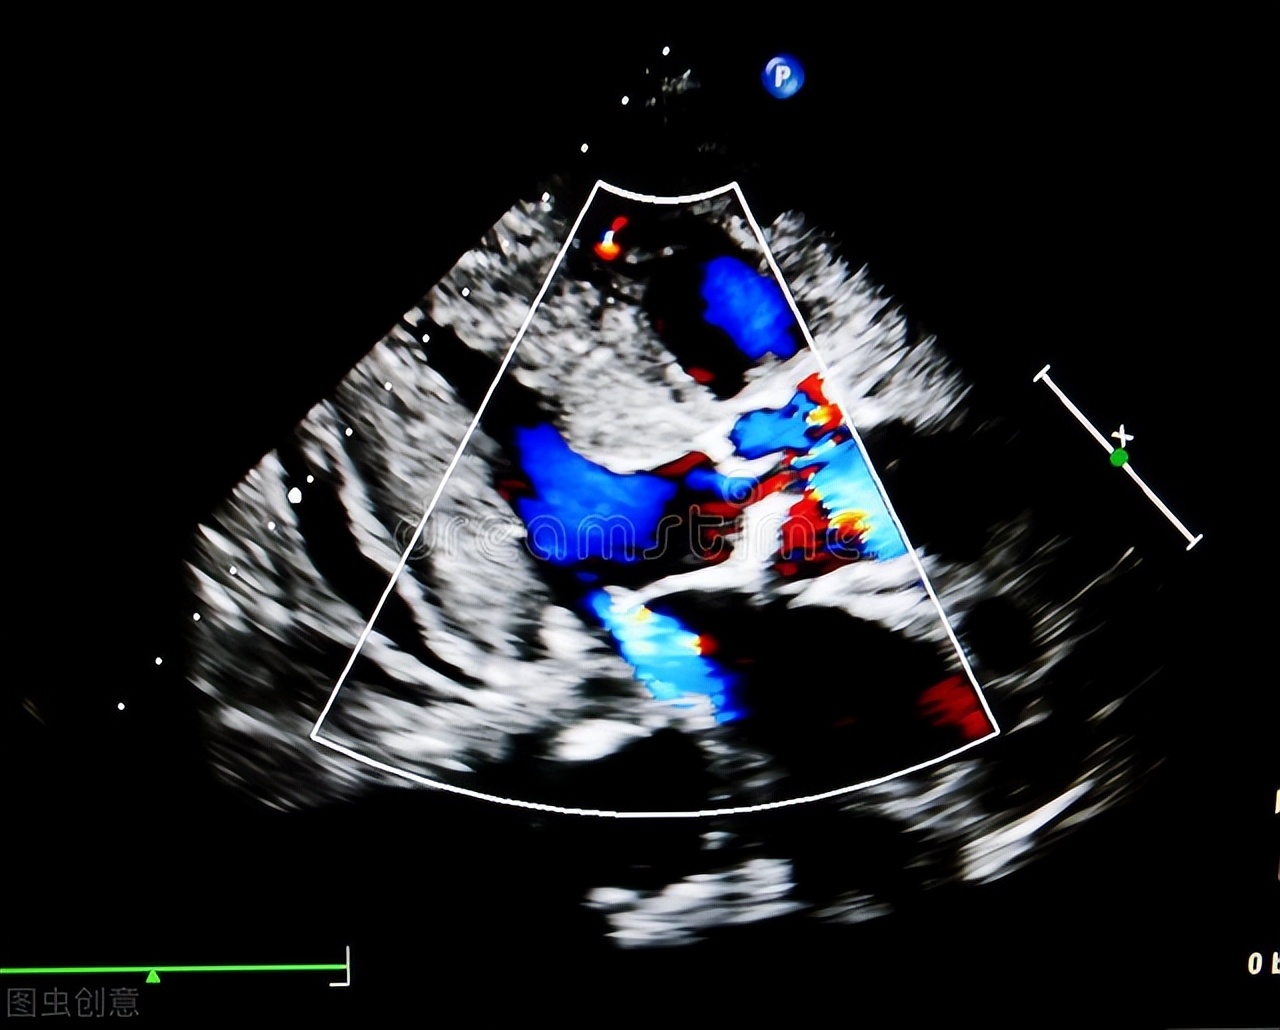

就在今年的体检中,林叔血压却出现了升高,达到了165/95mmhg,刚开始还不信,反复测量了几次都差不多。难道是现在吃的降压药不管用了?还是说疾病进展了?林叔也不敢自己擅自调药,于是带着疑问来到了心内科门诊。接诊医生接过体检报告,很快发现了端倪。因为他的 心脏彩超没有提示心房心室问题,射血分数也可以,心电图也没提示左心室高电压,说明这几年他的血压是控制达标的,没有出现相关并发症。